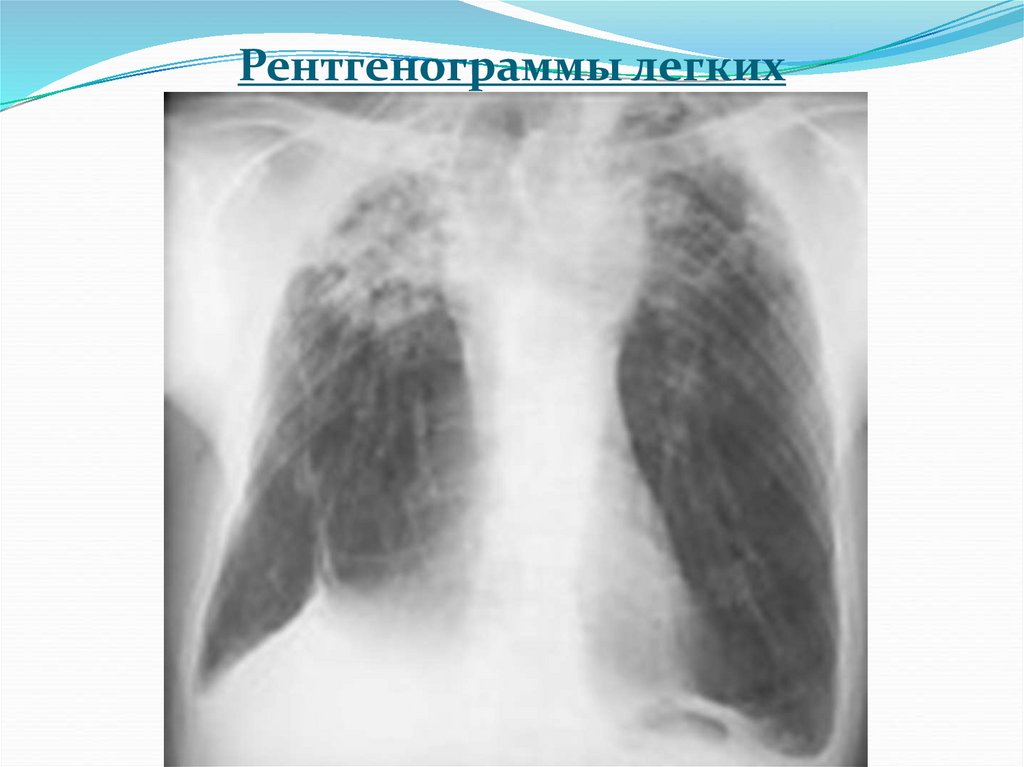

4. Рентгенограммы легких